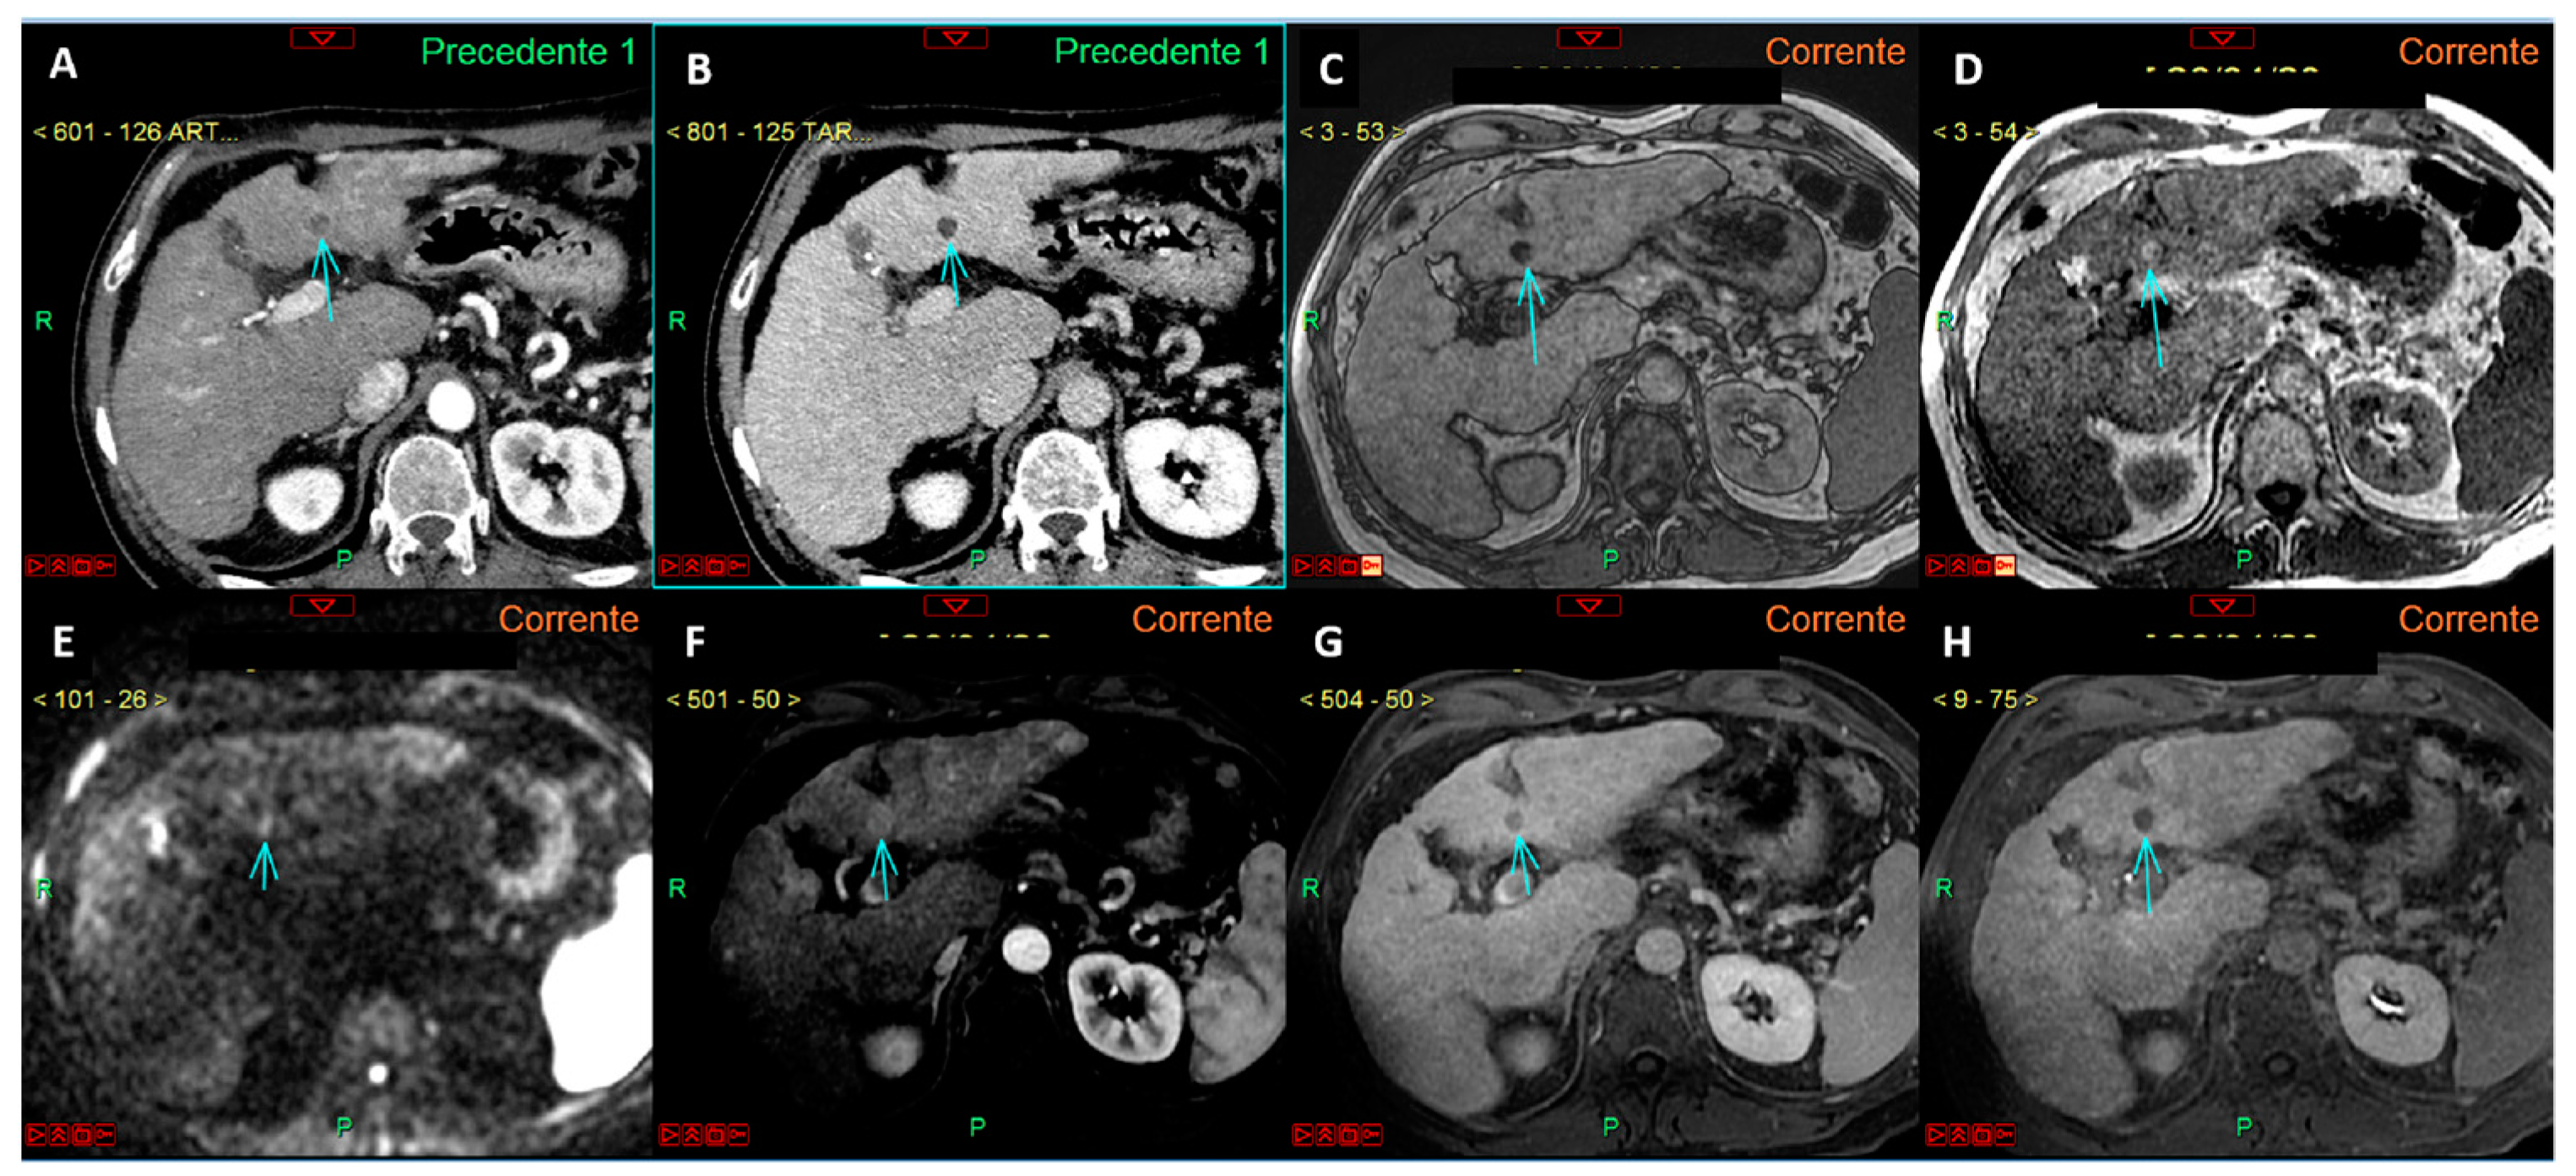

- Renzulli, M.; Biselli, M.; Brocchi, S.; Granito, A.; Vasuri, F.; Tovoli, F.; Sessagesimi, E.; Piscaglia, F.; D’Errico, A.; Bolondi, L.; et al. New hallmark of hepatocellular carcinoma, early hepatocellular carcinoma and high-grade dysplastic nodules on Gd-EOB-DTPA MRI in patients with cirrhosis: A new diagnostic algorithm. Gut 2018, 67, 1674–1682. [Google Scholar] [CrossRef]

- Renzulli, M.; Golfieri, R.; Bologna Liver Oncology Group (BLOG). Proposal of a new diagnostic algorithm for hepatocellular carcinoma based on the Japanese guidelines but adapted to the Western world for patients under surveillance for chronic liver disease. J. Gastroenterol. Hepatol. 2016, 31, 69–80. [Google Scholar] [CrossRef] [PubMed]

- Bouyer, T.; Roux, M.; Jacquemin, S.; Dioguardi Burgio, M.; Sutter, O.; Laurent-Croisé, V.; Lonjon, J.; Bricault, I.; Trillaud, H.; Rode, A.; et al. Detection of arterial phase hyperenhancement of small hepatocellular carcinoma with MRI: Comparison between single arterial and multi-arterial phases and between extracellular and hepatospecific contrast agents. Diagn. Interv. Imaging 2023, 104, 477–484. [Google Scholar] [CrossRef]